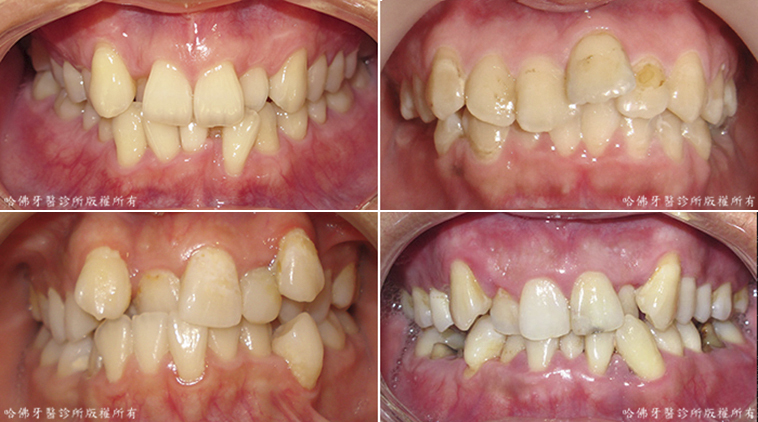

「前牙錯咬」是嚴重的咀嚼缺陷,它會使咀嚼時「錯咬」的前牙完全無法咀嚼食物,勉強咀嚼食物會令牙周組織產生物理傷害。最終,「前牙錯咬」可令該病患放棄整個前側牙齒的咀嚼功能(圖8)。

(圖8)「前牙錯咬」是嚴重的咀嚼缺陷,它會使咀嚼時「錯咬」的前牙完全無法咀嚼食物,勉強咀嚼食物會令牙周組織產生物理傷害。最終,「前牙錯咬」可令該病患放棄整個前側牙齒的咀嚼功能

「後牙錯咬」也是嚴重的咀嚼缺陷,它會使咀嚼時「錯咬」的後牙完全無法咀嚼食物,勉強咀嚼食物會令牙周組織產生物理傷害。最終,一個區域性的「後牙錯咬」卻可令該病患放棄該邊整體的咀嚼功能,而因此以小失大(圖9)。

(圖9)「後牙錯咬」也是嚴重的咀嚼缺陷, 它會使咀嚼時「錯咬」的後牙完全無法咀嚼食物,勉強咀嚼食物會令牙周組織產生物理傷害。最終,一個區域性的「後牙錯咬」卻可令該病患放棄該邊整體的咀嚼功能,而因此以小失大。